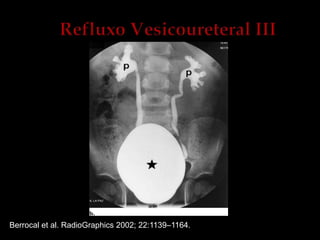

UCG: graduação do refluxo

Vesicoureteral Reflux and Reflux Nephropathy

Willian Carlos Nahas, Anuar Ibrahim Mitre, Sami Arap, Gilberto Menezes de Góes

Fernbach et al. RadioGraphics 2000; 20:155–168.

Refluxo 1º: O retorno de urina da bexiga para o uréter, conseqüência de uma

anomalia congênita da junção ureterovesical.

Hipoplasia de musculatura trigonal associada à diminuição do comprimento

do ureter submucoso

Refluxo 2º: é conseqüente à patologia obstrutiva intravesical, à disfunção

neuromuscular da bexiga ou outras anomalias, como válvula da uretra

posterior e ITU

Refluxo Ativo:o refluxo durante a micção

Refluxo Passivo: presente na fase de enchimento vesical

Berrocal et al. RadioGraphics 2002; 22:1139–1164.